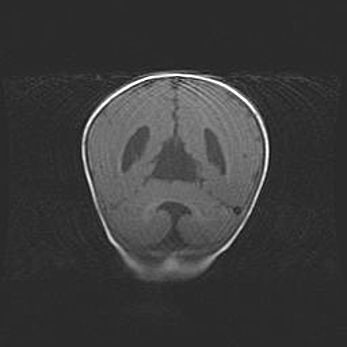

Открытая гидроцефалия.

Возраст: 9 месяцев 12 дней

Вес: 6800 г

Пол: мужской

Окружность головы: 41,5 см

Срок гестации: 28 недель

Гидроцефалия головного мозга у новорожденных имеет характерный признак: опережающий рост окружности головы приводит к визуально хорошо определяемой гидроцефальной форме сильно увеличенного в объёме черепа. Детские неврологи определяют следующие симптомы гидроцефалии у грудничков: выбухающий напряжённый родничок, частое запрокидывание головы, смещение глазных яблок к низу.